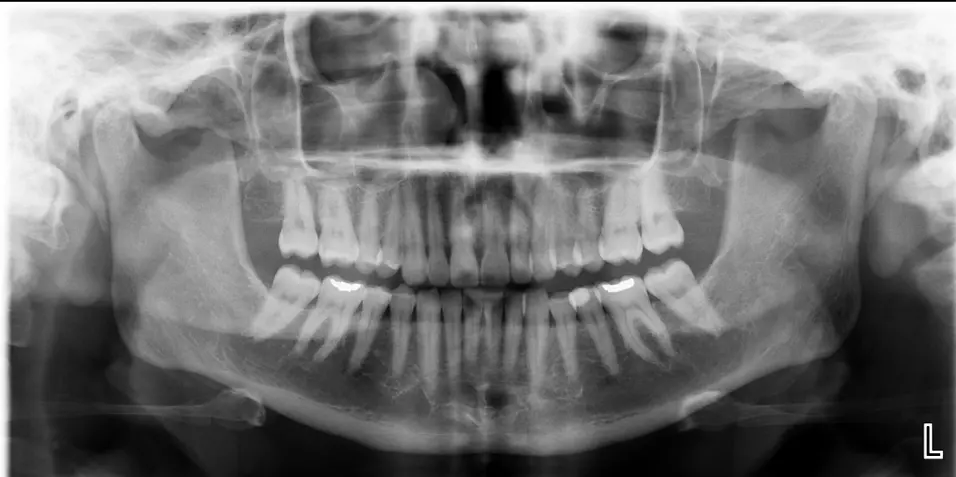

Accurate, rapid diagnostic analysis for panoramic, cephalometric, and periapical radiographs to support treatment planning.